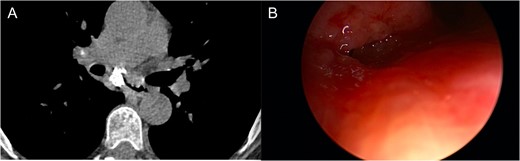

The patient was a 66-year-old white female with history of Histoplasmosis capsulatum infection and diabetes who presented as an outpatient with hemoptysis for 6 weeks. The patient was a lifelong non-smoker. A computer tomography (CT) scan of the chest revealed a calcified subcarinal lymph node along with an obstructing endobronchial lesion on the medial wall of the right mainstem bronchus (Fig. 1A). A rigid bronchoscopy was performed revealing an endobronchial mass causing a 50% obstruction of the right mainstem bronchus (Fig. 1B). The cryotherapy probe was used for mass excision and a full mediastinal staging was performed using endobronchial ultrasound (EBUS) bronchoscopy. The right mainstem bronchus was recanalized with return to 100% patency. Histology from the mass revealed an inflammatory polyp. The etiology of the inflammatory polyp was presumed to arise from inflammation stemming from the calcified station 7 lymph node abutting the medial wall of the right mainstem bronchus.

(A) Calcified subcarinal lymph node. (B) Obstructing endobronchial lesion on the medial wall of the right mainstem bronchus.